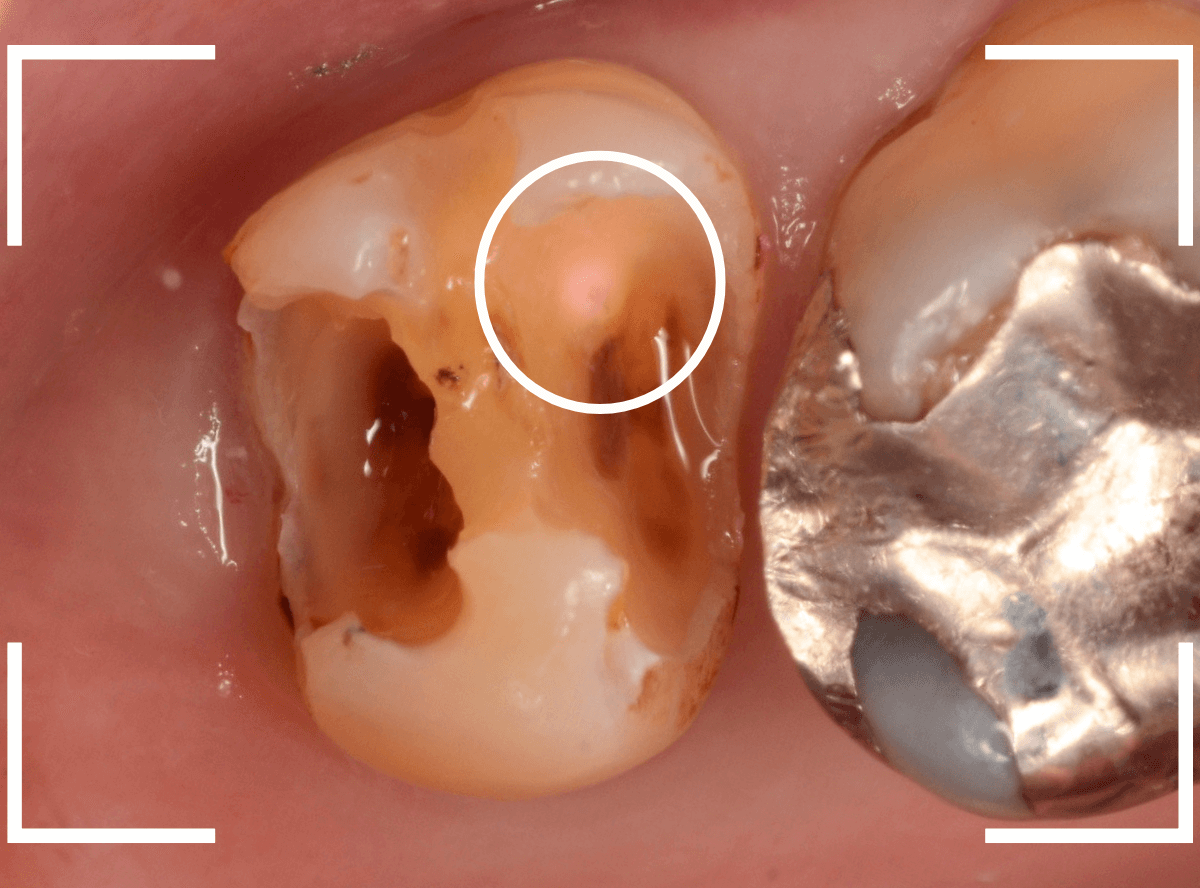

中のお薬も慎重に外して虫歯を除去します。

虫歯が深く、歯肉の下まで浸食していましたので、歯肉を部分切除し、虫歯を全て除去したところで、奇跡的に神経スレスレの状態でとどまっていました。

何とも言えませんが、神経を残せる可能性が出てきました。

虫歯が神経まで達していなくても、治療前から自発痛(何もしなくても痛い)があれば、神経をとらなければいけません。

今回は、そこまでの症状がありませんでしたので、患者さんと相談の上、神経を取らずに残す方法で様子を見る事になりました。

痛みが出ませんように。。。